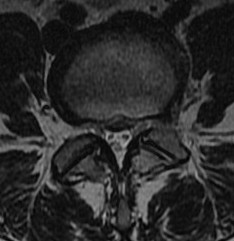

MRI

T2 Sagittal - myelogram

T1 Axial - see nerve root against white fat